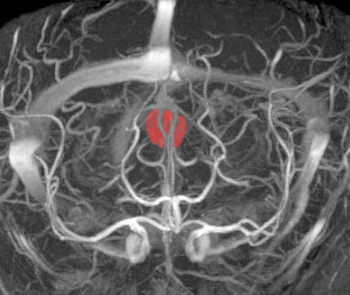

左側はMRI血管像です。赤く塗った松果体腫瘍がたくさんの血管とくに静脈に囲まれていて深い位置にあるのがわかります。右は手術後のMRIです。幸い後交連というところも残せたので眼球運動障害(ものが2重に見える)という後遺症は出ませんでした。